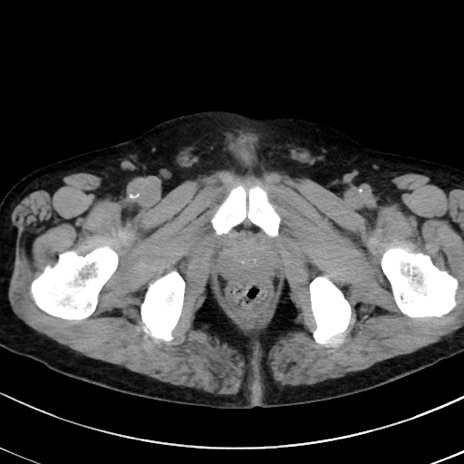

症例38(横断像)

冠状断像

【症例】70歳代 男性

【主訴】腹痛・嘔吐

【現病歴】昨晩より、嘔吐・腹痛あり。今朝になっても嘔吐あり。来院。

【既往歴】心臓バイパス手術、開腹胆摘、腸閉塞

【身体所見】BP 107/71mmHg、HR 116/min、腹部:平坦、軟、下腹部に軽度圧痛あり。反跳痛なし。

【データ】WBC 15100、CRP 0.32